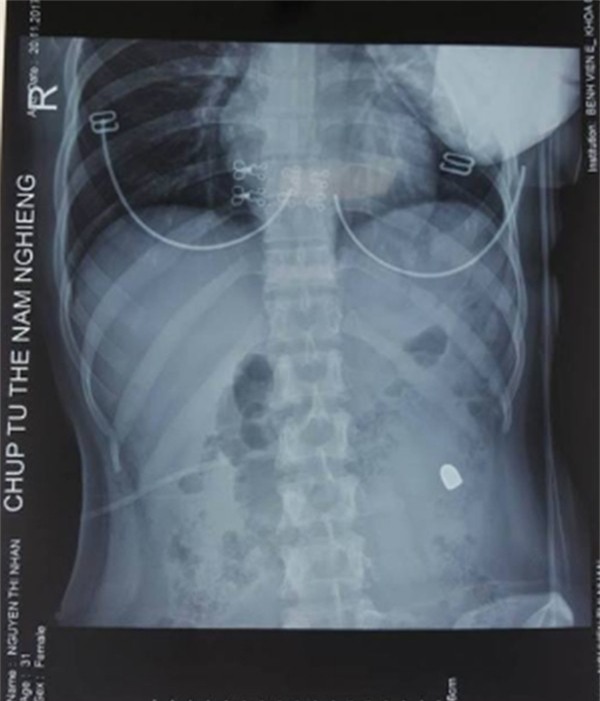

Phim chụp vết đạn bắn xuyên bụng cô gái

Các bác sĩ lập tức cho bệnh nhân đi siêu âm, chụp X-quang. Kết quả cho thấy, siêu âm có nhiều dịch trong ổ bụng, một đầu đạn nằm mạn sườn trái. Các bác sĩ chẩn đoán vết thương thấu bụng nghi ngờ thủng tạng rỗng. Ngay lập tức bệnh nhân này lên phòng mổ để cấp cứu cho bệnh nhân.